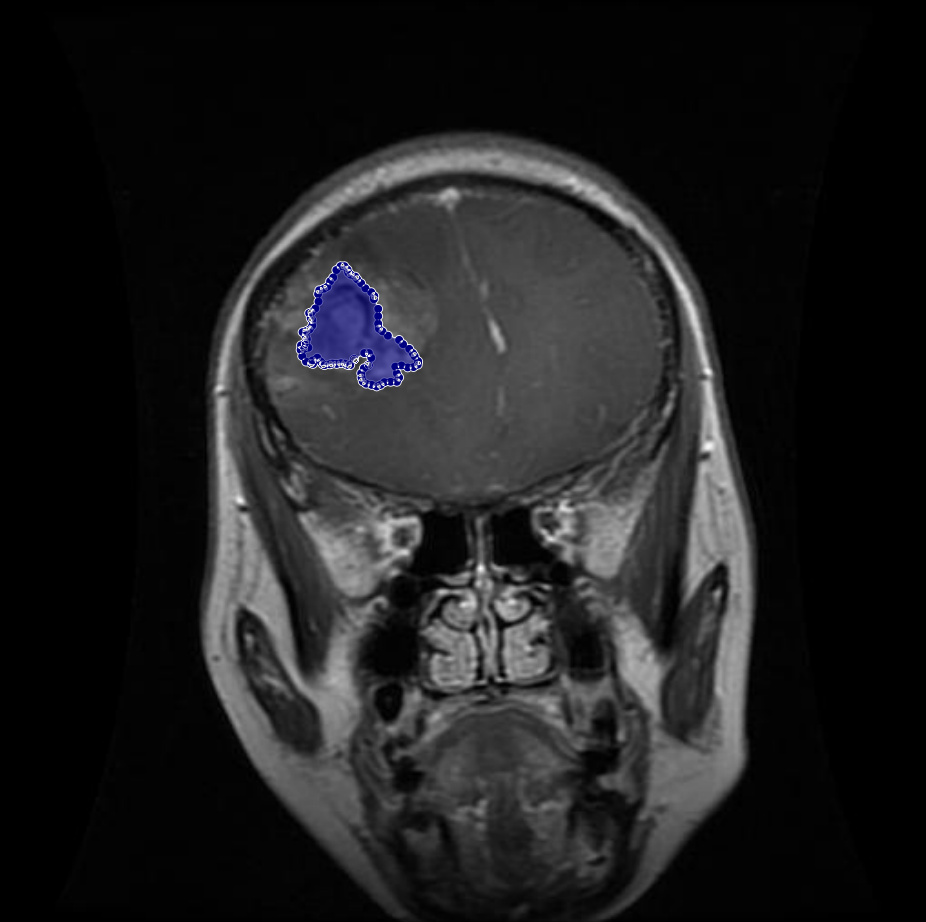

Figure 1: Samples of Glioma segmentation across different imaging planes

Glioma: Gliomas are irregularly shaped and often infiltrate surrounding tissues, presenting significant challenges for precise boundary definition. These complexities require robust segmentation techniques to capture their variable morphology. As shown in Figure 1, gliomas exhibit irregular and diffuse growth patterns, which are highlighted through annotated tumor masks.